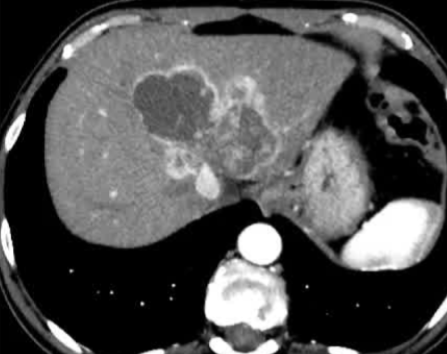

· 单中心、样本量小; 83 岁的女性,体重超标 40 毫米单发 ICC(S7-S8) 中肝静脉和右肝静脉浸润性,活检:非酒精性脂肪性肝炎(慢性肝病),马斯氏(MaS)病(30%)

考虑采用“三步策略 TARE→ PVE → Surgery”方案 剂量活性:1.56 和 3.16 GBq